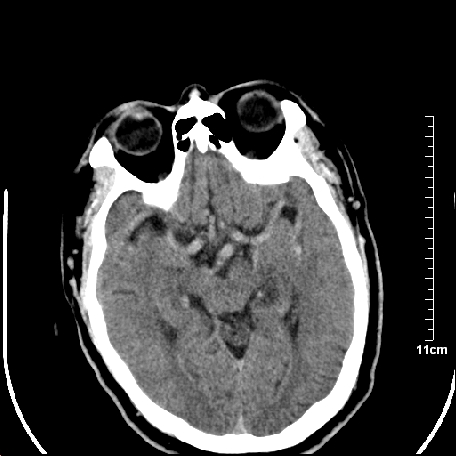

2.老年脑,基底动脉硬化迂曲。

基底动脉硬化迂曲。高血红蛋白血症。

颅内未见明显创伤性影像,建议上传骨窗,看看左侧颧弓